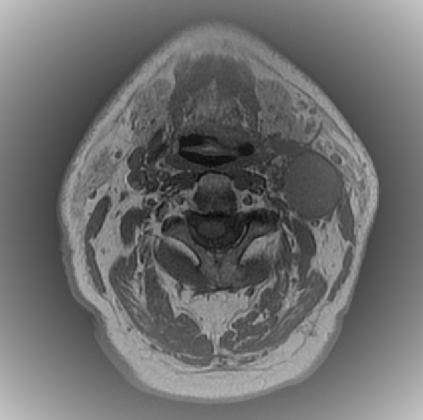

Organ at risk (OAR) segmentation is a critical process in radiotherapy treatment planning such as head and neck tumors. Nevertheless, in clinical practice, radiation oncologists predominantly perform OAR segmentations manually on CT scans. This manual process is highly time-consuming and expensive, limiting the number of patients who can receive timely radiotherapy. Additionally, CT scans offer lower soft-tissue contrast compared to MRI. Despite MRI providing superior soft-tissue visualization, its time-consuming nature makes it infeasible for real-time treatment planning. To address these challenges, we propose a method called SegReg, which utilizes Elastic Symmetric Normalization for registering MRI to perform OAR segmentation. SegReg outperforms the CT-only baseline by 16.78% in mDSC and 18.77% in mIoU, showing that it effectively combines the geometric accuracy of CT with the superior soft-tissue contrast of MRI, making accurate automated OAR segmentation for clinical practice become possible. See project website https://steve-zeyu-zhang.github.io/SegReg